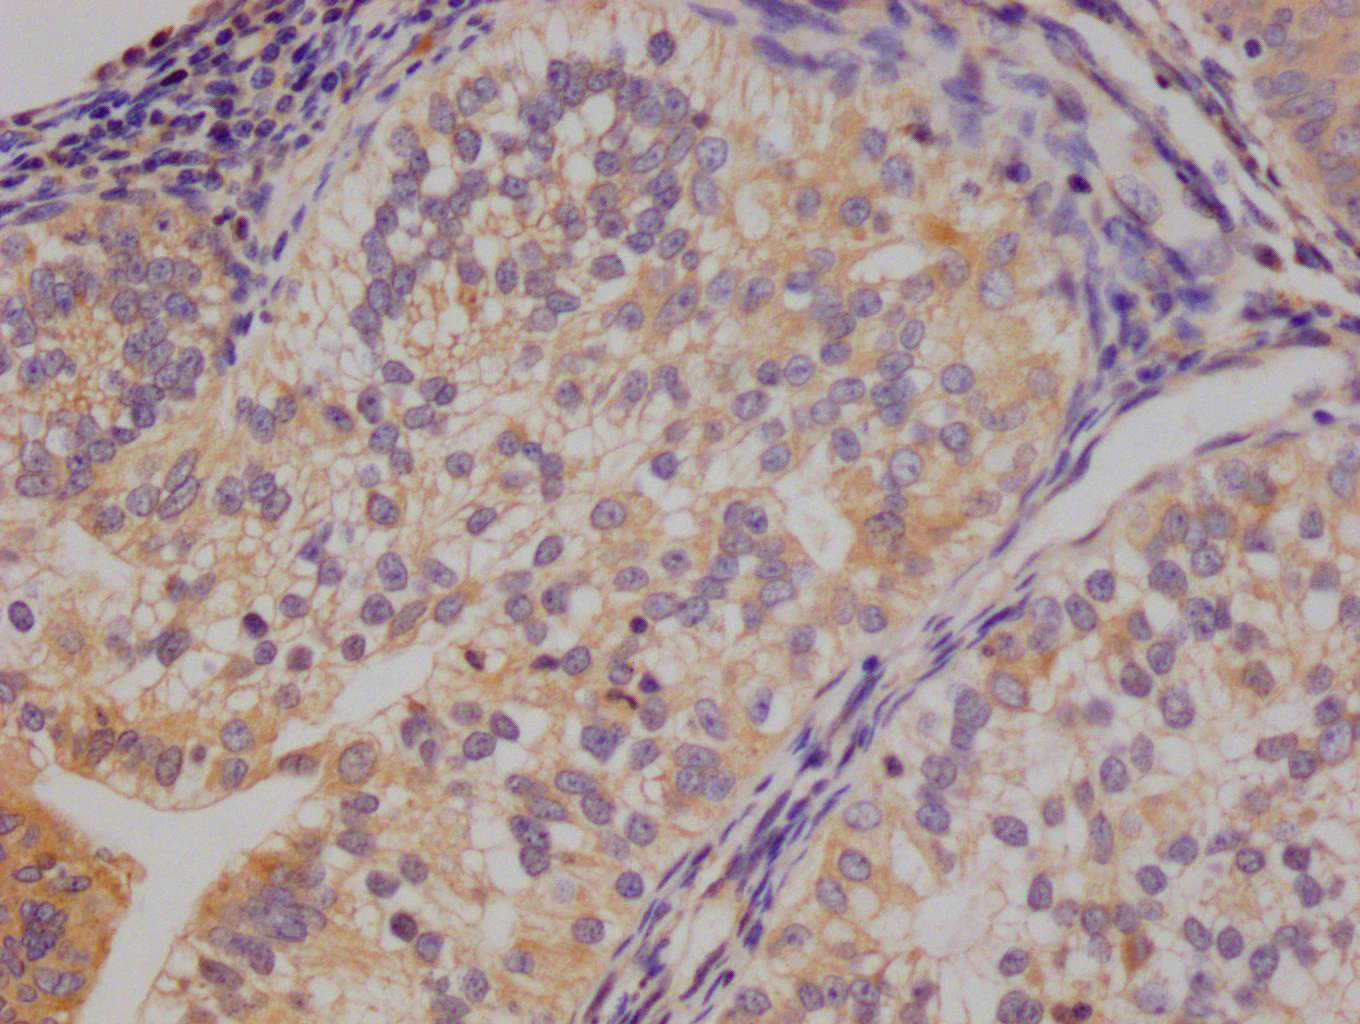

圖片:

應(yīng)用范圍:ELISA, IHC

Application Recommended Dilution IHC 1:20-1:200 -